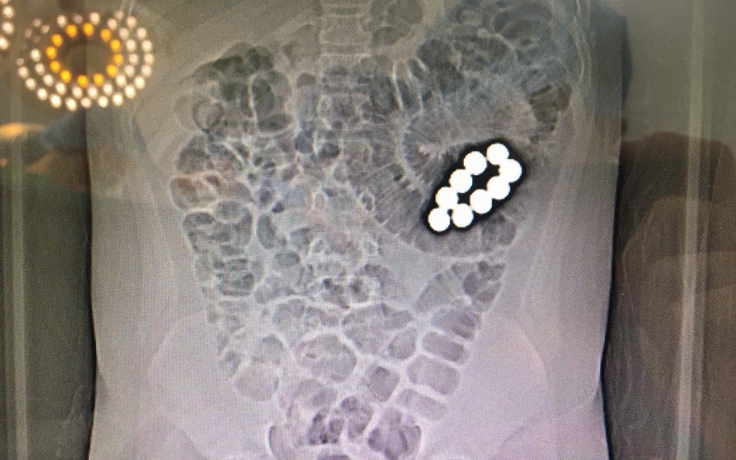

Bé trai 10 tuổi cấp cứu vì nuốt 9 viên bi sắt vào bụng

Bé trai 10 tuổi phải nhập viện cấp cứu vì bị tắc ruột hoàn toàn do nuốt 9 viên bi vào trong ổ bụng.